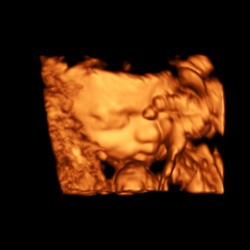

Afgelopen dinsdag de 13 weken echo gehad van ons 🫶🏼je. We hebben 2 hele mooie foto’s mee gekregen en de rest van de foto’s is op een usb stick gezet, eenmaal thuis aangekomen snel de usb stick in de laptop gestopt! Wat bleek de lieve dame had een kort filmpje gemaakt waarbij ons dotje aan het duimen was 🥰 zo verliefd!

Dit is mijn 13 weken echo met 13+4 dagen. Wat denken jullie wat het wordt q ...

Vandaag de 13 weken echo gehad van onze tweeling. Alles was goed en ze lagen er als fotomodelletjes bij dat we binnen een half uur weer buiten stonden 😅. Zo verliefd en blij ❤️ (bovenste foto is kindje 1 aan het drinken)